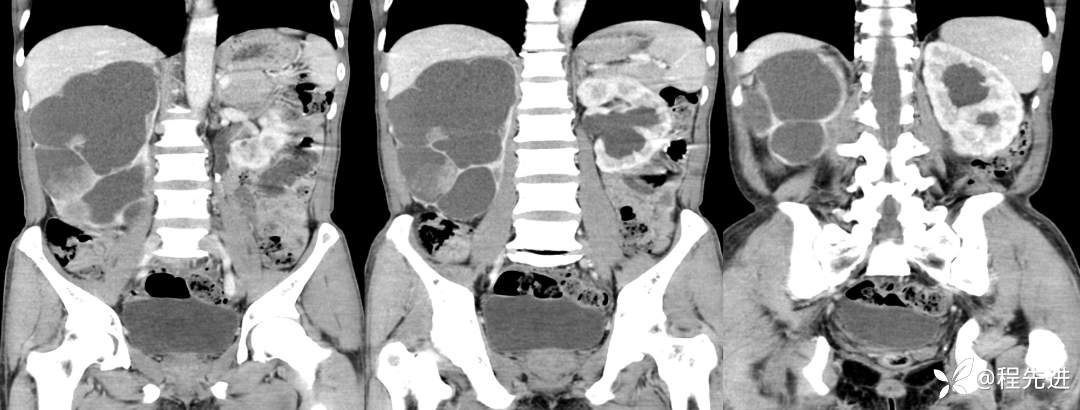

冠状位重建